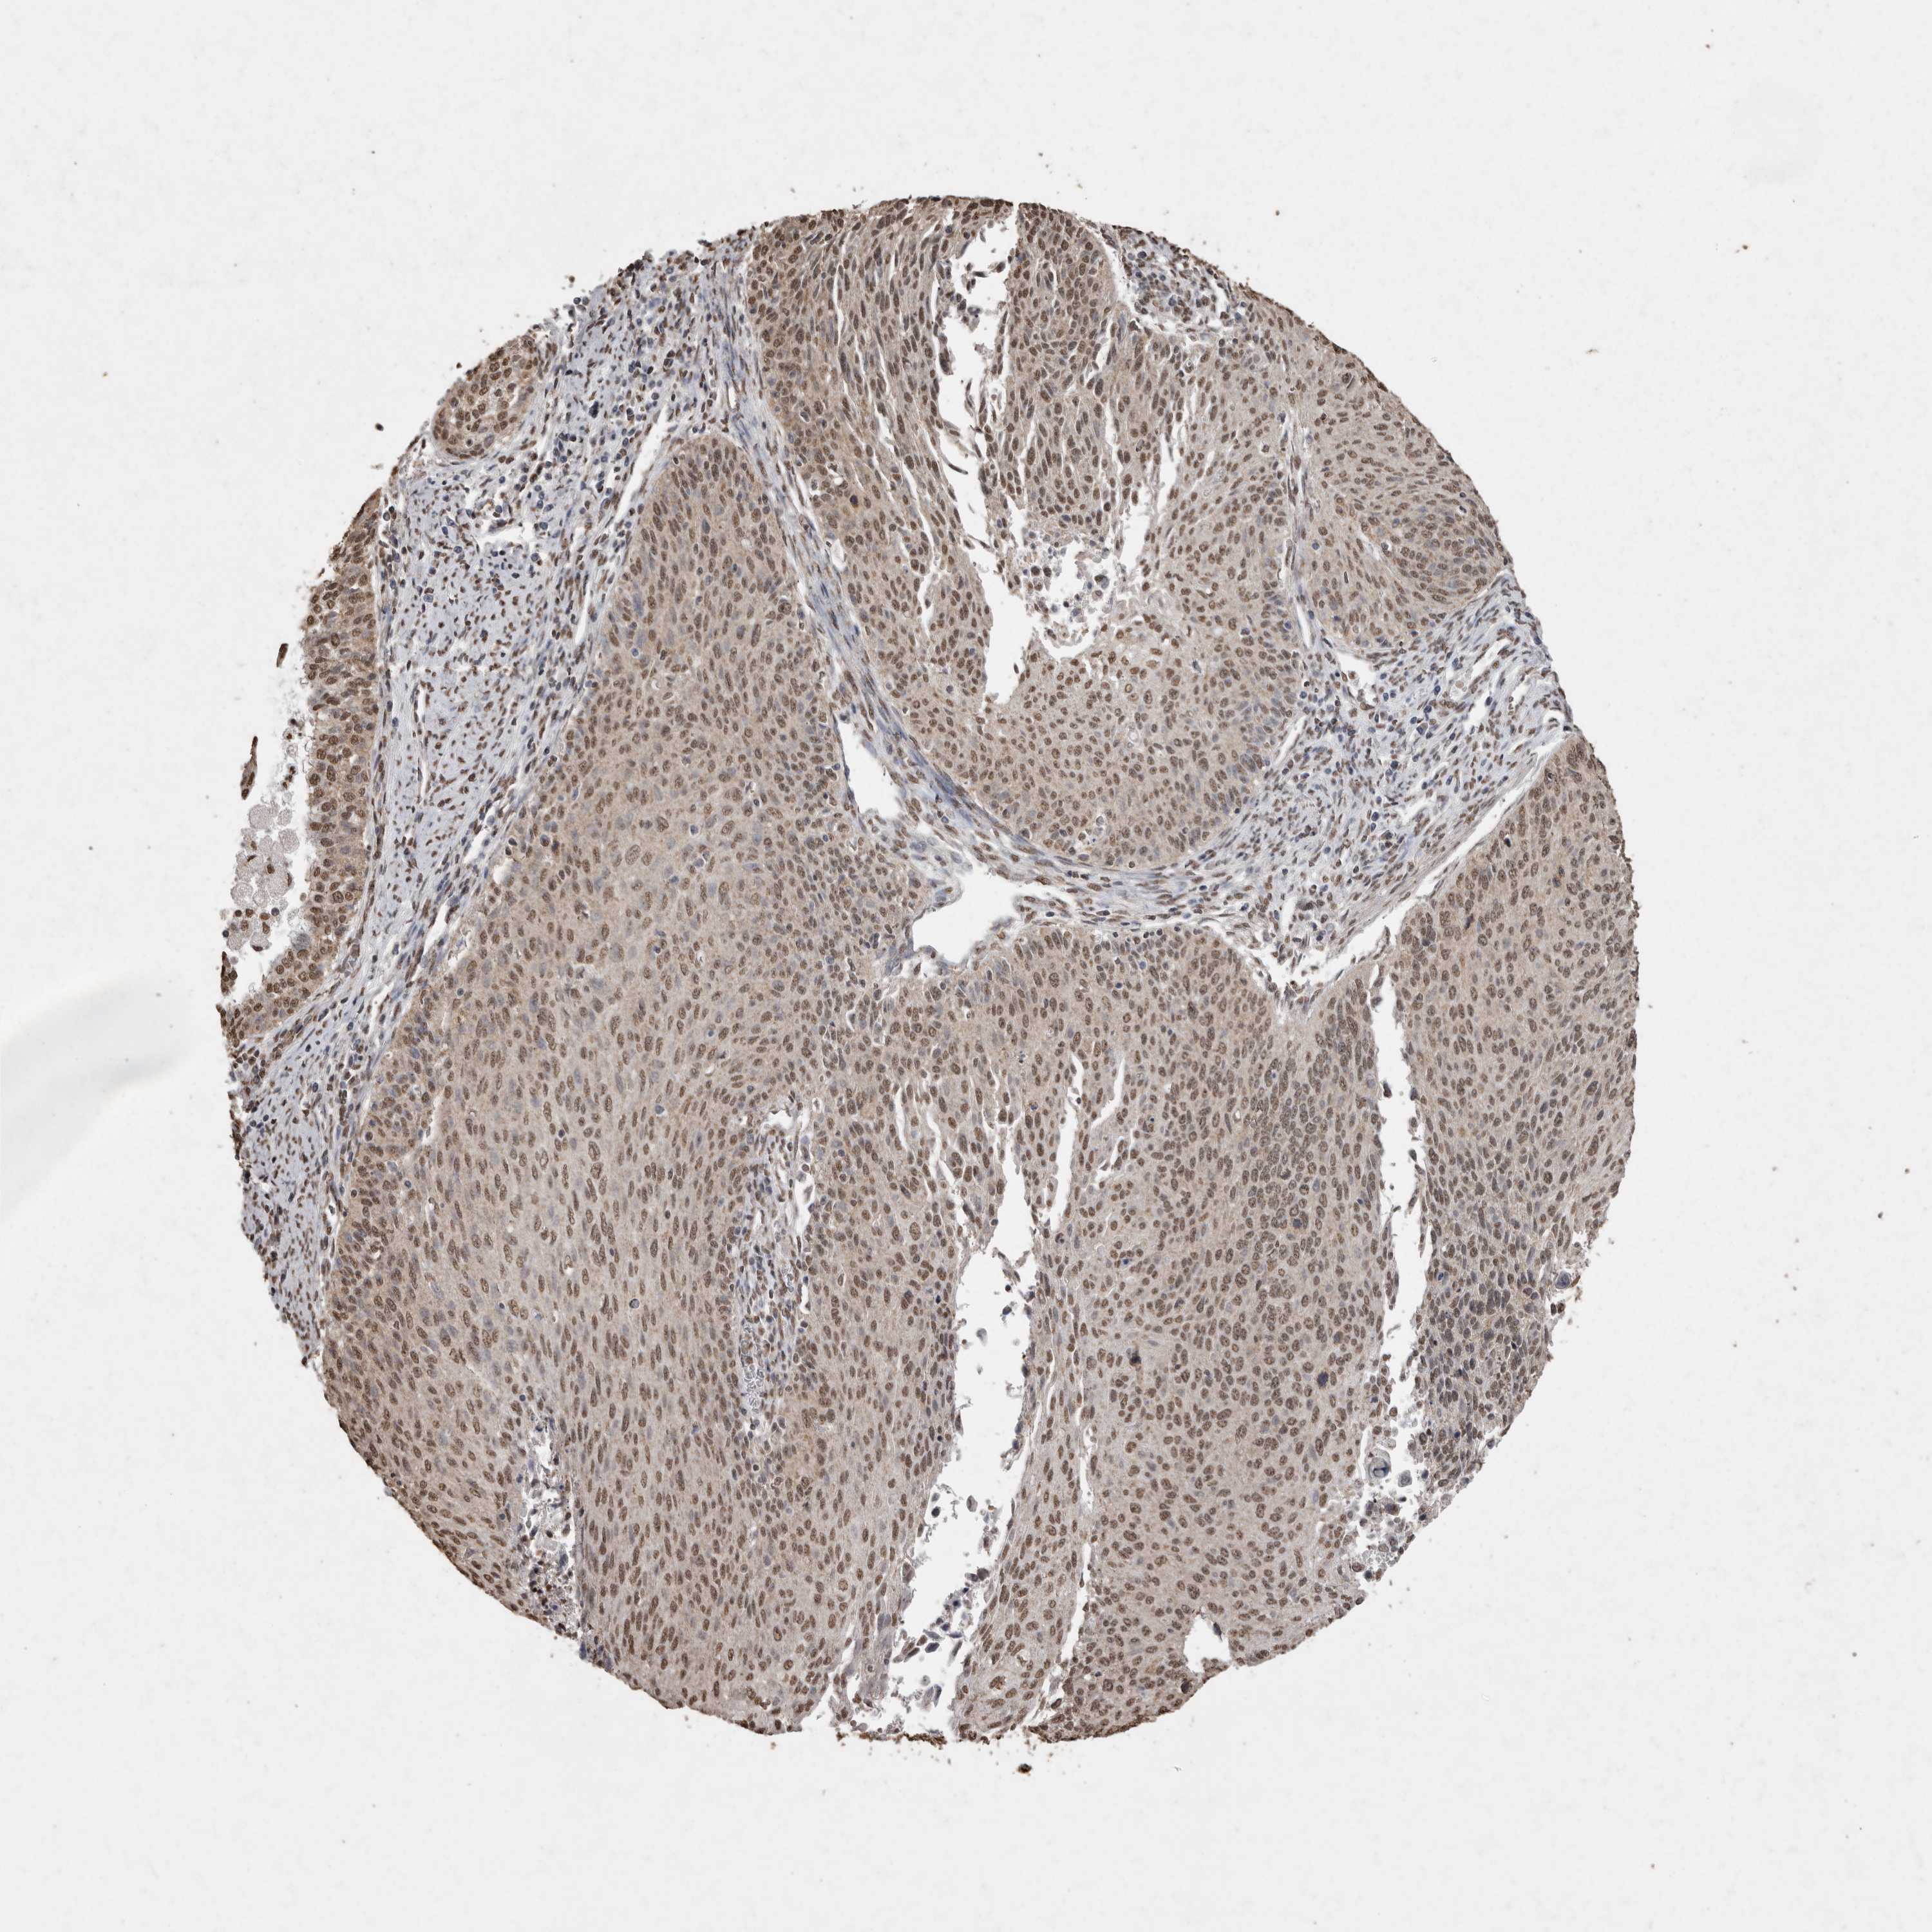

CERVICAL CANCER - Protein expressioni

A mouse-over function shows sample information and annotation data. Click on an image to view it in a full screen mode. Samples can be filtered based on level of antibody staining by selecting one or several of the following categories: high, medium, low and not detected. The assay and annotation is described here.

Note that samples used for immunohistochemistry by the Human Protein Atlas do not correspond to samples in the TCGA dataset.

Antibody stainingi

Antibody staining in the annotated cell types in the current human tissue is reported as not detected, low, medium, or high, based on conventional immunohistochemistry profiling in selected tissues. This score is based on the combination of the staining intensity and fraction of stained cells.

Each image is clickable and will lead to virtual microscopy that enables deeper exploration of all samples and also displays staining intensity scores, fraction scores and subcellular localization as well as patient and tissue information for each sample.

Antibody HPA028897

Antibody CAB026212

Staining

High

Medium

Low

Not detected

Intensity

Strong

Moderate

Weak

Negative

Quantity

>75%

75%-25%

<25%

None

Location

Nuclear

Cytoplasmic/membranous

Cytoplasmic/membranous,nuclear

Squamous cell carcinoma, NOS